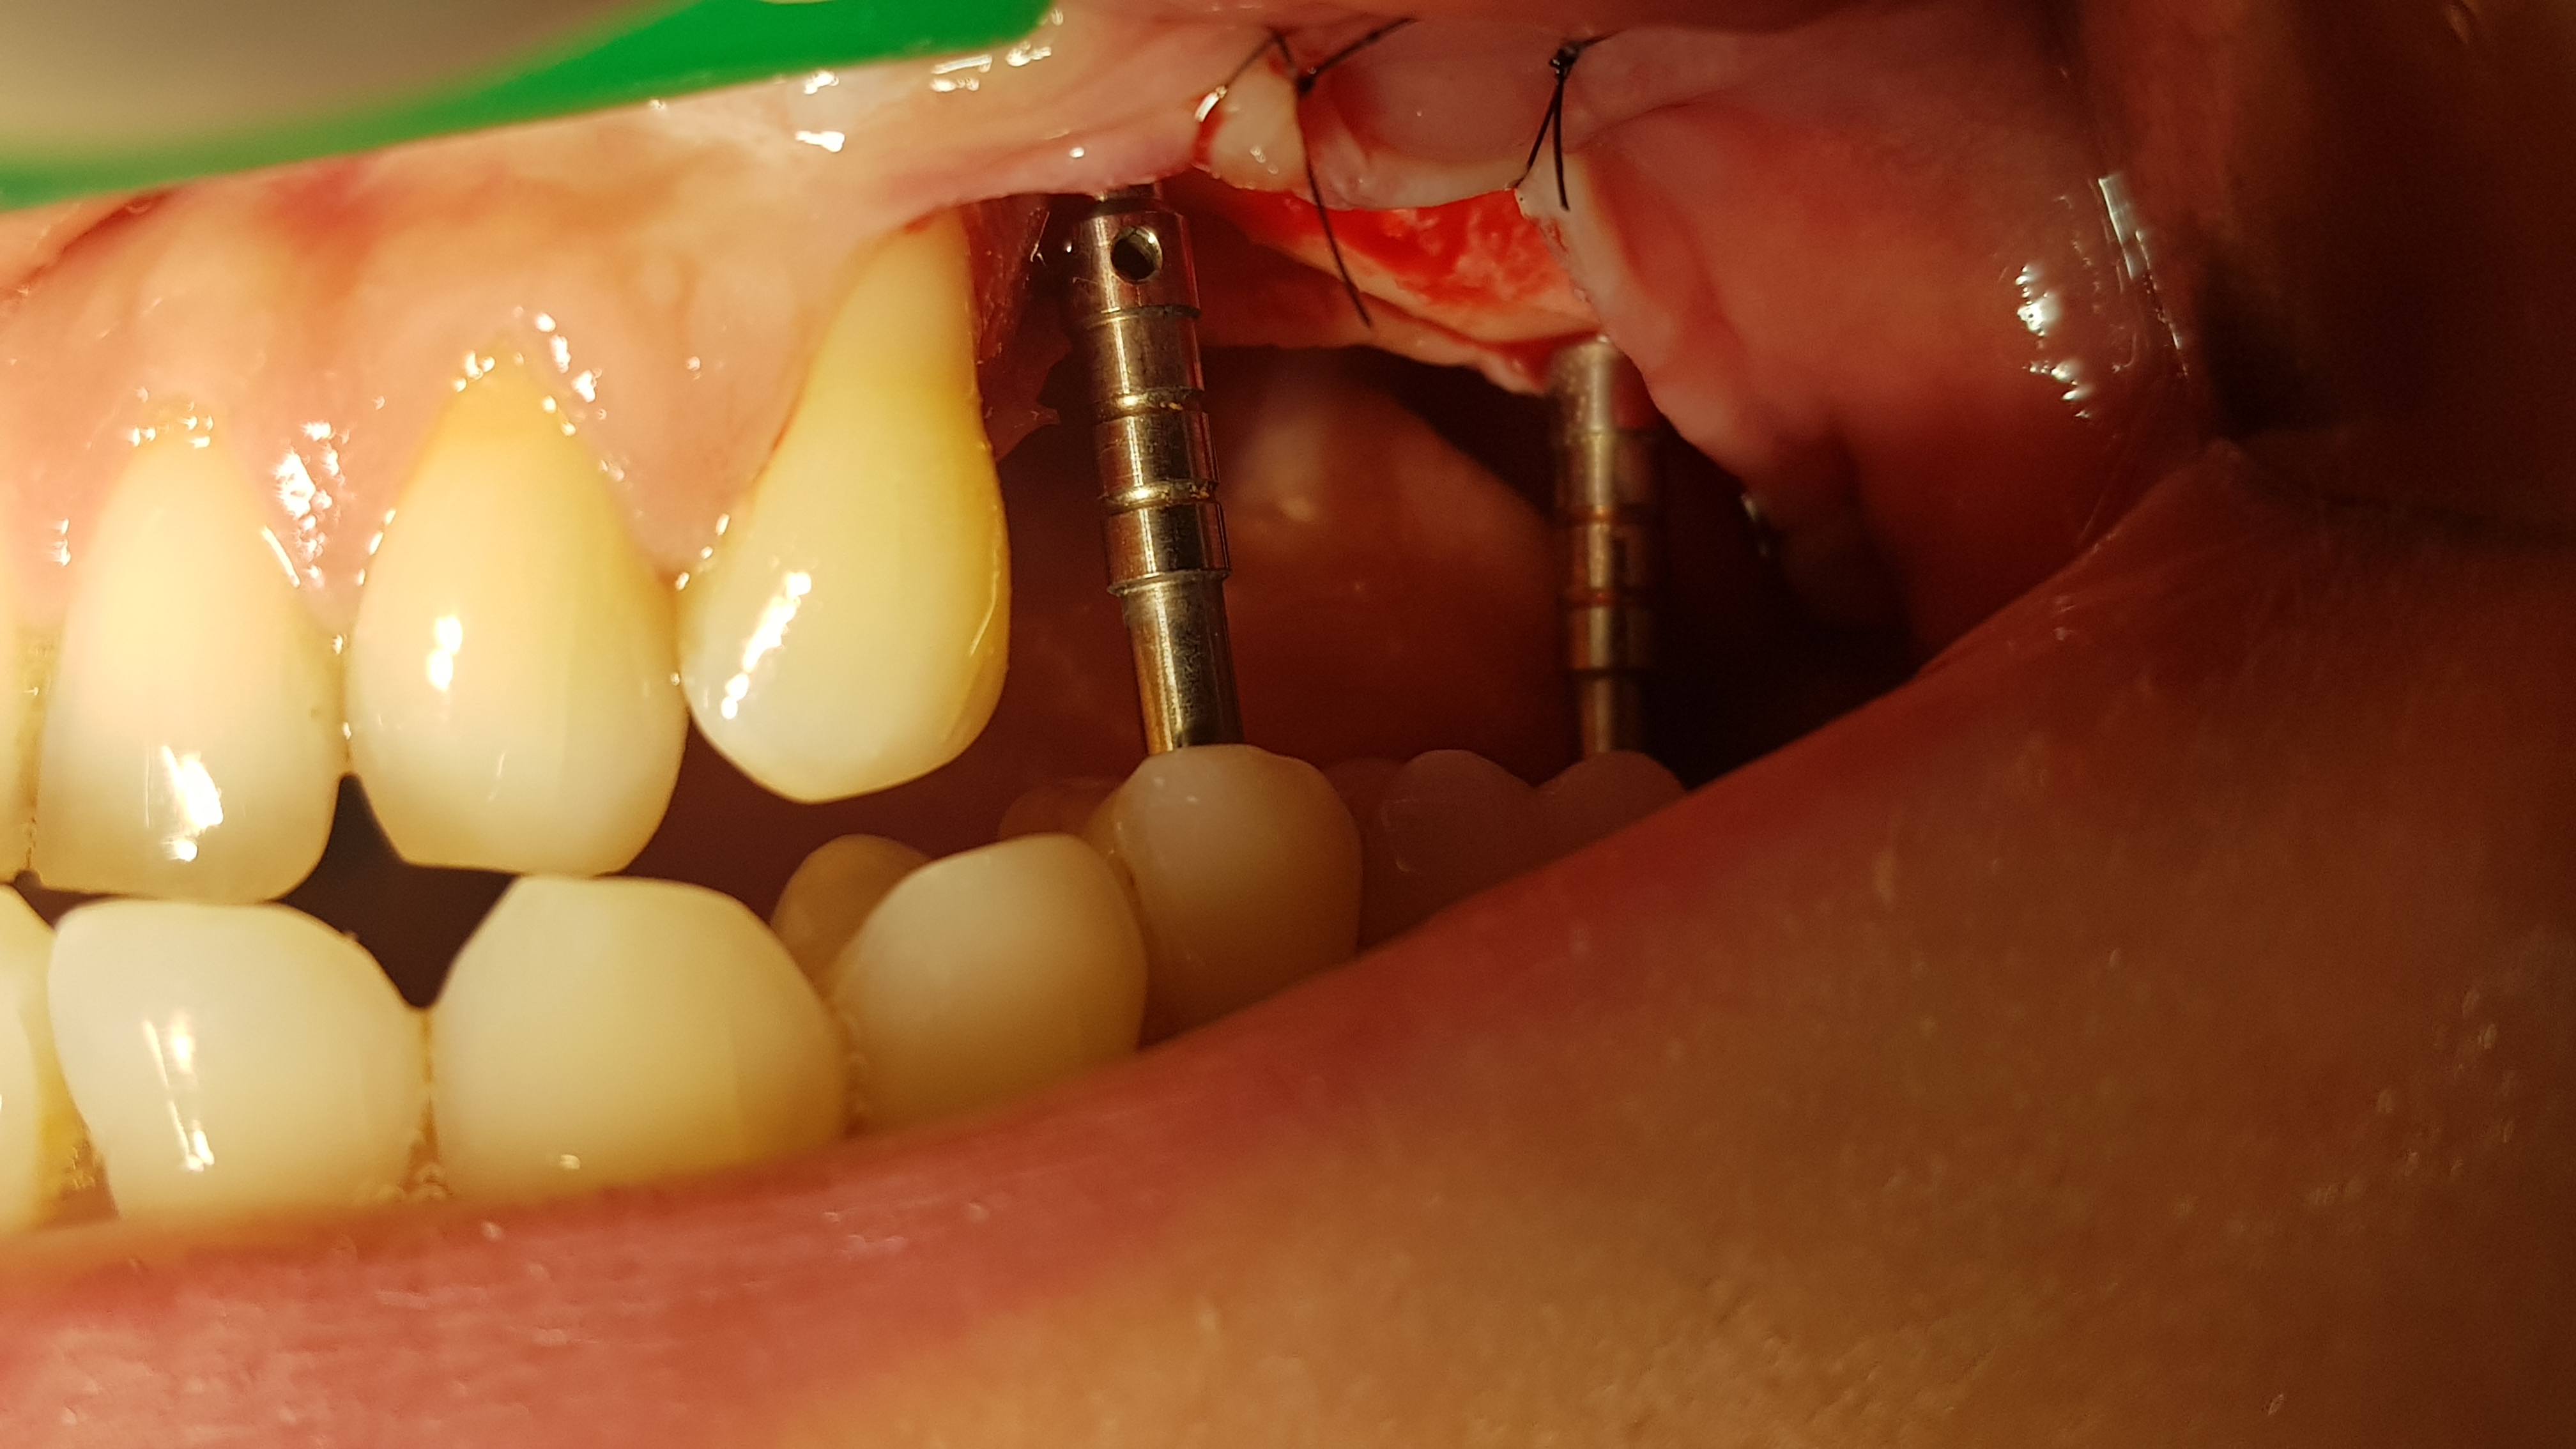

Regenerację blaszki przedsionkowej potwierdzono także klinicznie po odwarstwieniu płata podczas zabiegu planowej implantacji. Zmierzono szerokość wyrostka na poziomie 7-8 mm (ryc.14). Po wyrównaniu płaszczyzny wyrostka (ryc. 15) wykonano łoża dla implantów śrubowych w okolicy 45 (dł. 10 mm, śr. 3.7 mm) i 46/47 (dł. 10 mm, śr. 4.1 mm) (ryc.16), które wprowadzono w kość z momentem obrotowym około 25 Ncm. Ranę zaopatrzono szwami (PTFE – politetrafluoroetylen 4-0, igła odwrotnie tnąca, profil 3/8 koła długość 16 mm) (ryc.17).

Ryc. 14. Pomiar szerokości szczytu wyrostka w okolicy 45 wykazuje około 7 mm.

Ryc. 15. Pozycjonowanie implantów.

Ryc. 16. Wprowadzenie implantów w okolicy 45(3.7,10 mm) i 46-47( 4.1,10 mm). Ryc. 17. Zaopatrzenie rany.